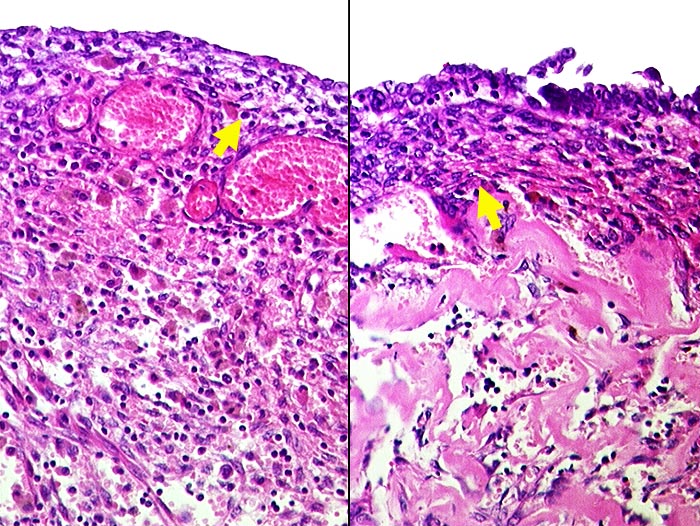

Endometriose

Metaplasie / Heterotopie

Ovar

Auskleidung einer Schokoladezyste: links im Bild fehlt das Epithel. Ein schmaler Streifen endometranes Stroma ist sichtbar. Darunter zahlreiche Hämosiderinhaltige Makrophagen. Rechts ist das Epithel erhalten.

Prallelastische Zyste mit 10ml dunkelbrauner Flüssigkeit.

Schokoladezyste. V.a. Endometriose.